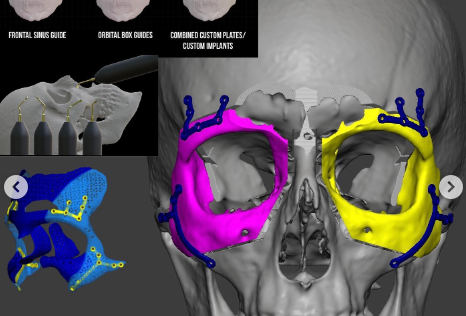

Orbital Box Osteotomy

This is an advanced and very risky procedure for repositioning the entire eye socket to correct congenital deformities, trauma, or severe asymmetry.Overview

Incisions are made around the orbit, often combining eyelid, conjunctival, and sometimes craniofacial approaches.Bones of the orbit are carefully cut, mobilized, and repositioned.

Titanium plates or screws are used to secure the new orbital position.

Pros:

Corrects severe orbital deformities and asymmetryCan significantly improve both function and aesthetics

Provides permanent structural correction

Cons:

Highly complex and requires craniofacial surgical expertiseLonger recovery (4–6 weeks) and potential hospitalization

Risks include vision changes, bleeding, infection, and nerve injury

ORBITAL BOX OSTEOTOMY BEFORE & AFTER

Price: €8,000–€25,000